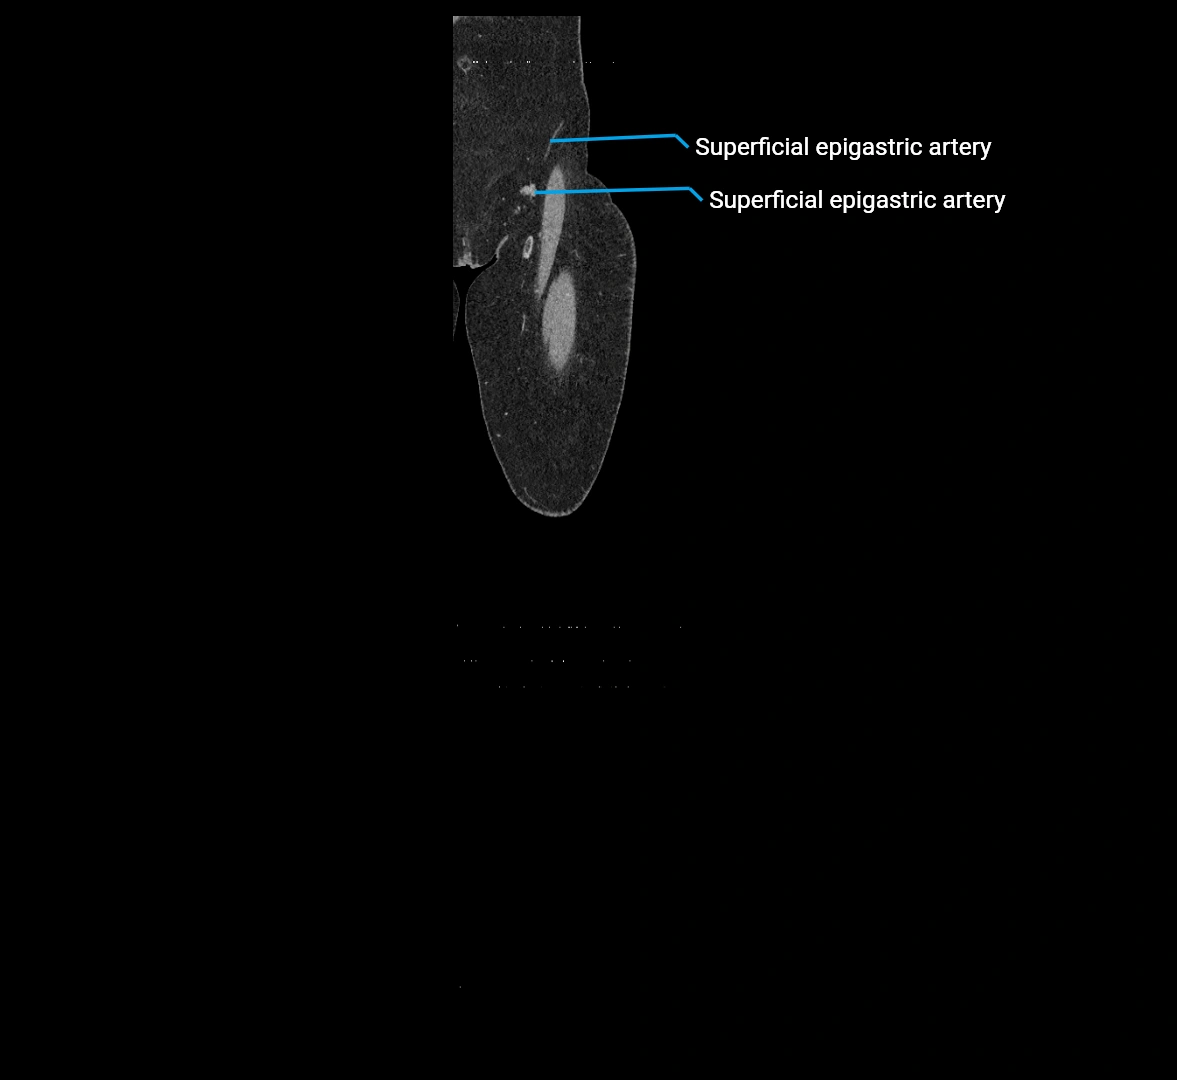

MRI images

image